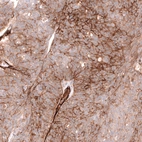

Immunohistochemistry analysis in human placenta and liver tissues using AMAb91815 antibody. Corresponding MCAM RNA-seq data are presented for the same tissues.